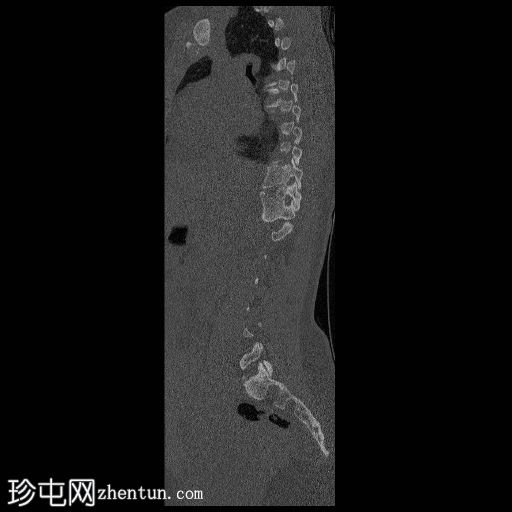

CT

矢状位骨窗

胸腰段交界处可见右侧完全节段性半椎体(轴位/矢状位/冠状位)。

未见与上方或下方相邻椎体融合的迹象。